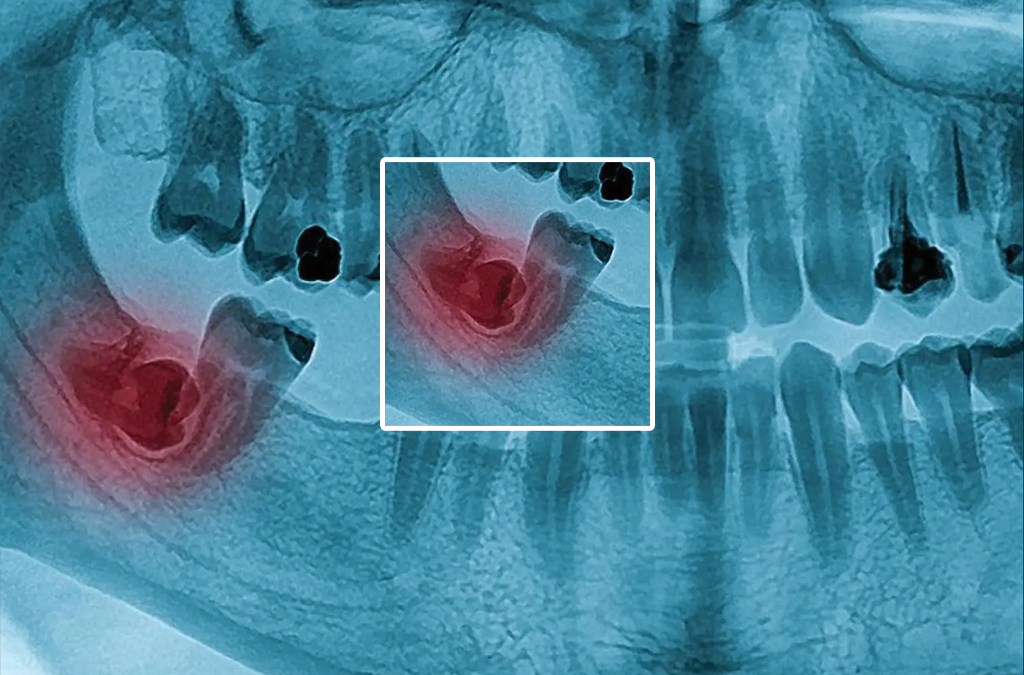

Wisdom teeth are the last set of permanent teeth that erupt at the back of the mouth – two each on the upper and lower jaw. They are the third molars that fall as eight teeth when counted from the front central tooth. They usually appear between 17-25 years of age. Some people might never develop wisdom teeth or even if it develops it stays as submerged teeth.